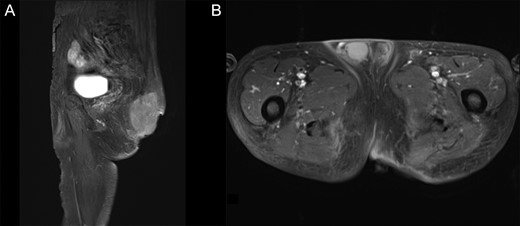

Pre-operative T1WI contrast-enhanced MRI with fat suppression. (A) Sagittal image. (B) Axial image. The protruding tumor was resected, and the internal tumors showed no considerable changes in size.

Two months after initial examination, the patient was hospitalized at our department. To prevent a secondary infection from defecation, we first performed an artificial anastomosis. Mohs’ paste was subsequently applied a total of 16 times over 3 months. The wound infection improved 2 weeks after administering Mohs’ paste and antibiotics (ampicillin/sulbactam). After the infection subsided, three courses of neoadjuvant chemotherapy (Doxorubicin) were performed. The disintegrated portion of the tumor recessed by using Mohs’ paste, and the bleeding, exudation and odor subsided. Moreover, the patient was able to tolerate both sitting and supine positions (Fig. 1B). The contrast-enhanced MRI revealed that the protruding area of the tumor was resected with no increase in the internal tumor size (Fig. 3A and B). One day prior to curative surgery, embolization of the left inferior gluteal artery.